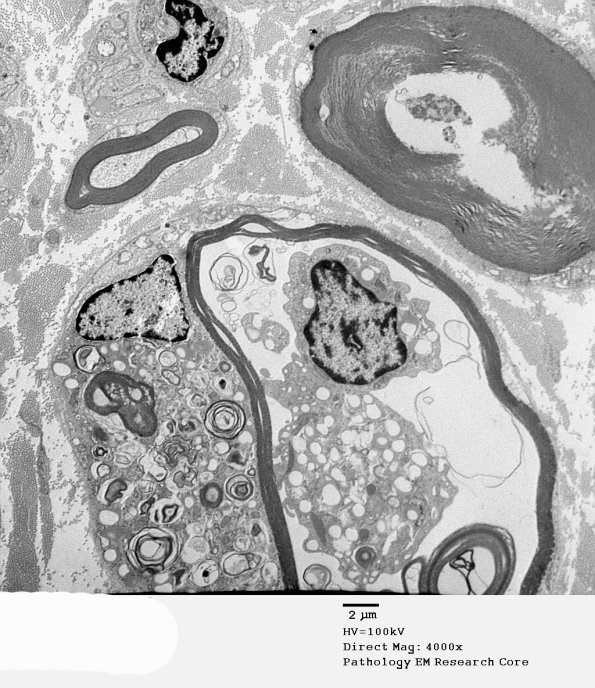

2B4,5 The macrophage is within the myelin sheath which is degenerating as is the adjacent axon. (electron micrographs)